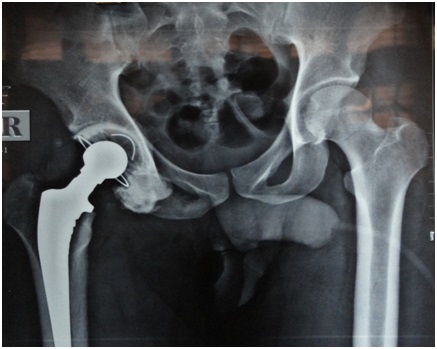

Radiological evaluation was done in the form of X-ray and MRI. X-ray of the pelvis with both hip joints (Figure 2) showed inferior dislocation of the femur with features suggestive of avascular necrosis of the head of the femur and flattening of the weight bearing dome of the acetabulum. MRI (Figure 3) showed a similar picture with conformation of antero-inferior dislocation of hip. The patient was advised total hip replacement and all pre-operative investigations were within normal limits.

Figure 2: X-ray of pelvis with both hips showing inferior dislocation of right hip